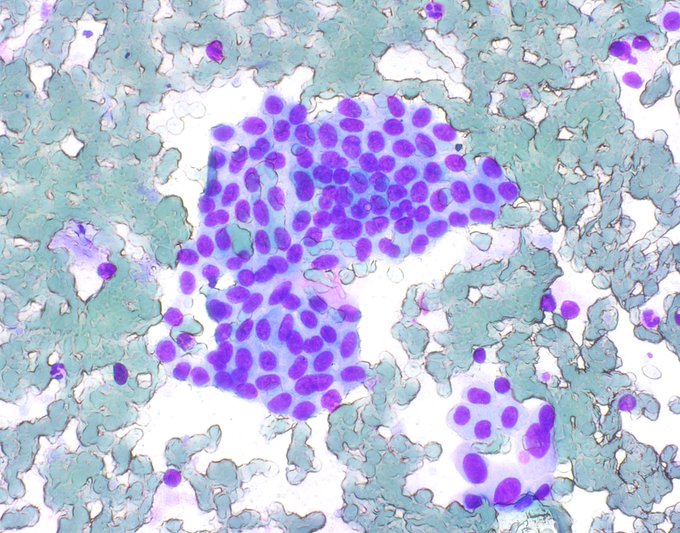

FNA of a gallbladder mass. Diagnosis?

This one has written all over it.

is going to make the diagnosis in the blink of an eye . . . this one took me a couple beats.